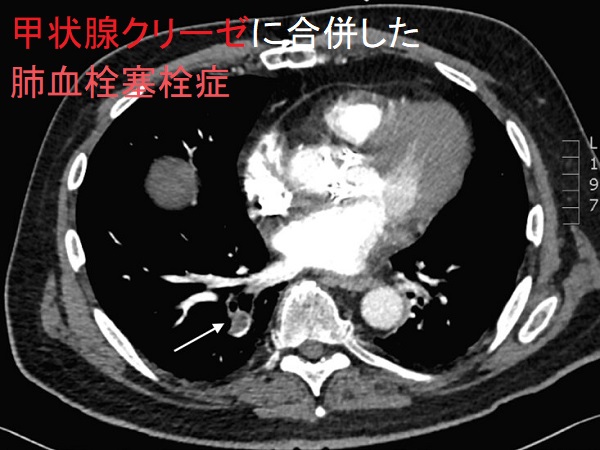

甲状腺クリーゼに肺血栓塞栓症を合併[Clin Pract Cases Emerg Med. 2020 Nov;4(4):540-543.]

甲状腺クリーゼに肺血栓塞栓症(肺梗塞)、横紋筋融解症を合併した報告があります[Clin Pract Cases Emerg Med. 2020 Nov;4(4):540-543.]

- 胸部造影CTでほぼ確定